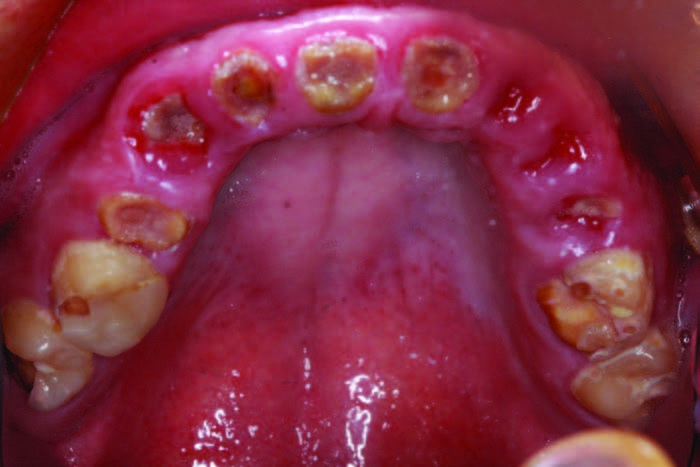

A 26-year-old male was diagnosed with hydrocephaly in utero. Hydrocephalus is a condition where there is an excessive accumulation of cerebral spinal fluid around the brain. Individuals affected with hydrocephalus often have impaired cognitive and physical development.[1,2] He was born into a loving family, but when his mother passed away from cancer, his father was unable to take care of a son with emotional and learning disabilities. This young man went on to have a terminal dentition due to poor oral habits. His grandparents stepped in and have been as supportive as possible, even while he has been living in a group home. They requested a treatment plan that would allow their grandson, whose teeth had been ravaged by soda, the dignity of having his smile replaced with implants. The patient’s Mountain Dew habit had destroyed his smile and self-esteem (Figure 1). The patient’s chronic soda habit with a lack of oversight at his group home led to gross generalized caries. Figure 2).